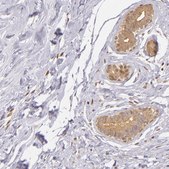

Anti-IMPDH2 antibody produced in rabbit, a Prestige Antibody, is developed and validated by the Human Protein Atlas (HPA) project . Each antibody is tested by immunohistochemistry against hundreds of normal and disease tissues. These images can be viewed on the Human Protein Atlas (HPA) site by clicking on the Image Gallery link. The antibodies are also tested using immunofluorescence and western blotting. To view these protocols and other useful information about Prestige Antibodies and the HPA, visit sigma.com/prestige.

• IHC tissue array of 44 normal human tissues and 20 of the most common cancer type tissues.